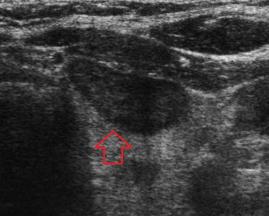

- Tiroid iltihabı (Hashimoto)

- Hashimato'da lazer tedavisi: İlaç dozlarının azaltılması veya kesilmesi ve kilo kontrolü !!!

- Hashimoto hastalığında destek tedavileri